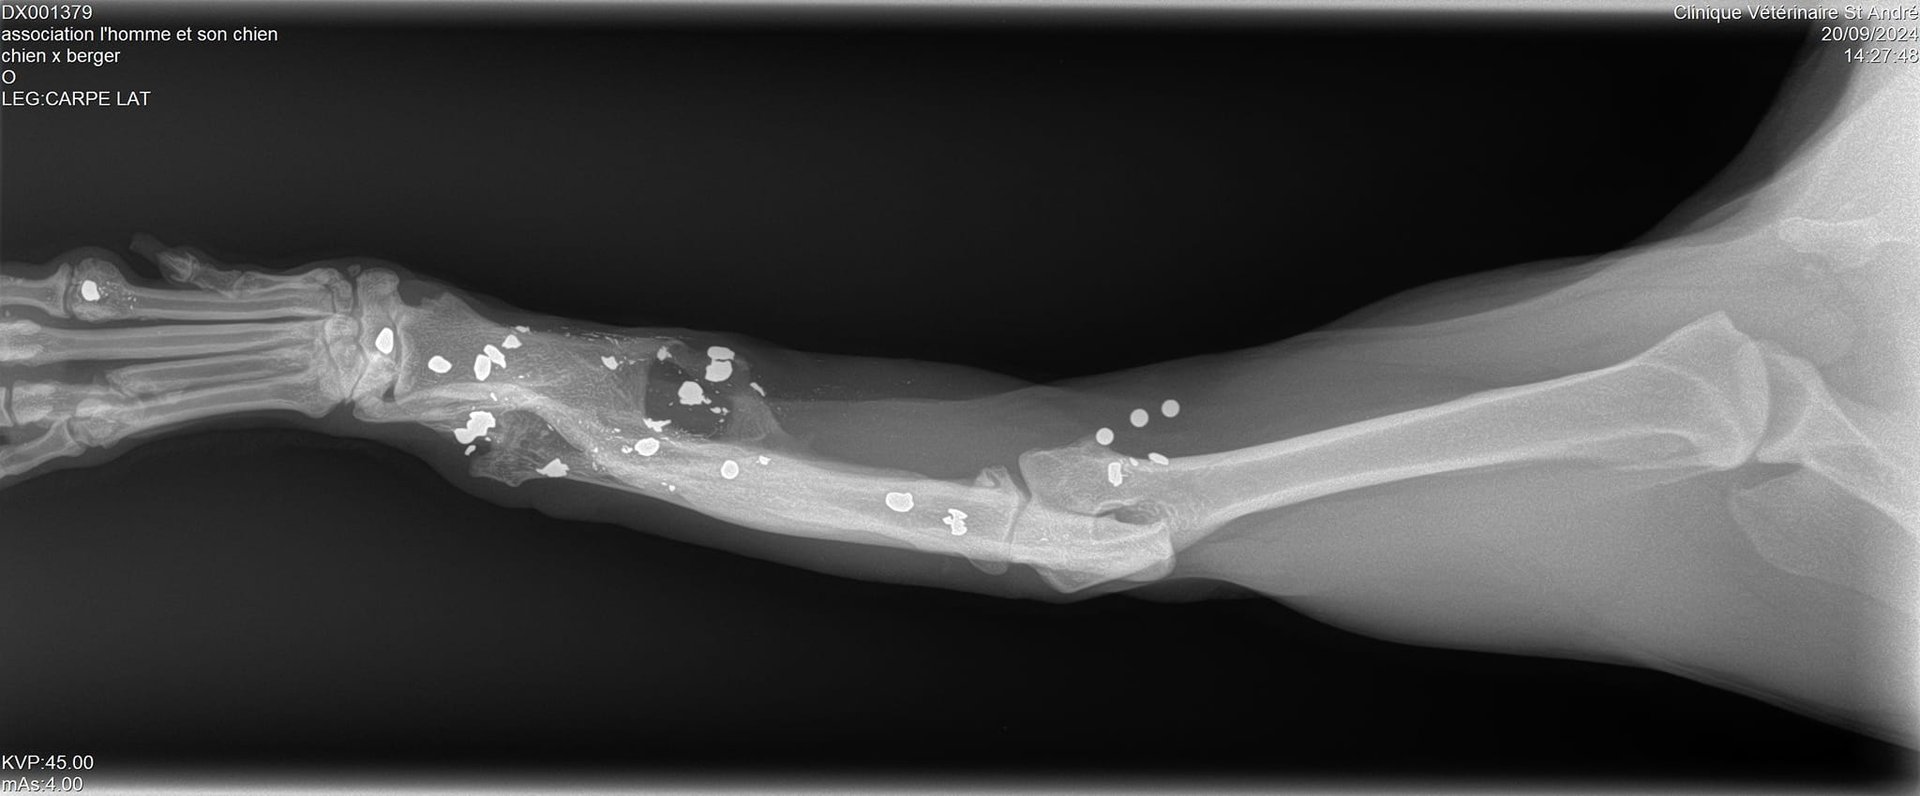

Sa patte avant gauche, criblée de balles, est détruite et, malgré ça, il est obligé de s'en servir car il ne pose pas toujours sa patte arrière droite…

Vous allez halluciner en voyant ses radios !